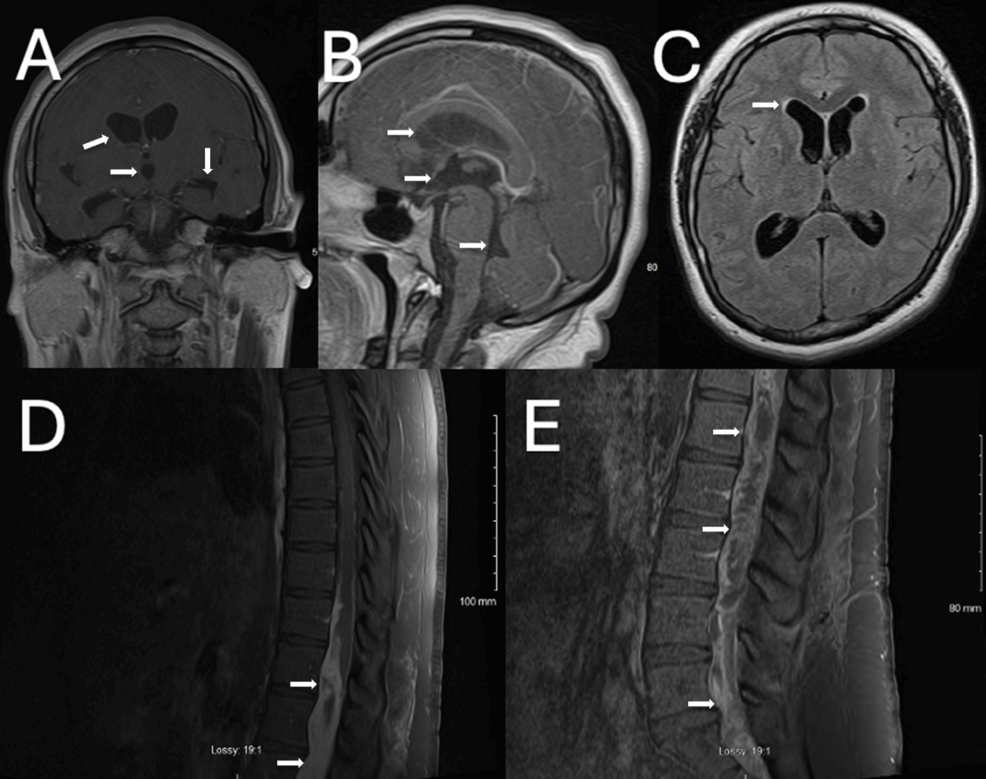

Myxopapillary ependymomas are slow-growing tumors that typically arise in the spinal cord, most commonly in the conus medullaris and filum terminale regions. While often presenting with localized pain, weakness, or bowel/bladder dysfunction, the case reported in Cureus highlights an atypical presentation: recurrent syncope. **Syncope**, or fainting, occurs when there’s a temporary reduction in blood flow to the brain. In this instance, the tumor’s location and growth were compressing vital structures, ultimately leading to the episodes of unconsciousness. This underscores the importance of considering atypical presentations of these tumors, particularly when neurological symptoms are present.

Syncope is a common symptom with a broad differential diagnosis, ranging from benign causes like vasovagal syncope to more serious cardiac arrhythmias. This makes pinpointing the underlying cause challenging. The Cureus case emphasizes that in patients with unexplained, recurrent syncope, particularly those with subtle neurological findings, a thorough investigation including spinal MRI should be considered. The delay in diagnosis in this case highlights the need for increased awareness among clinicians.